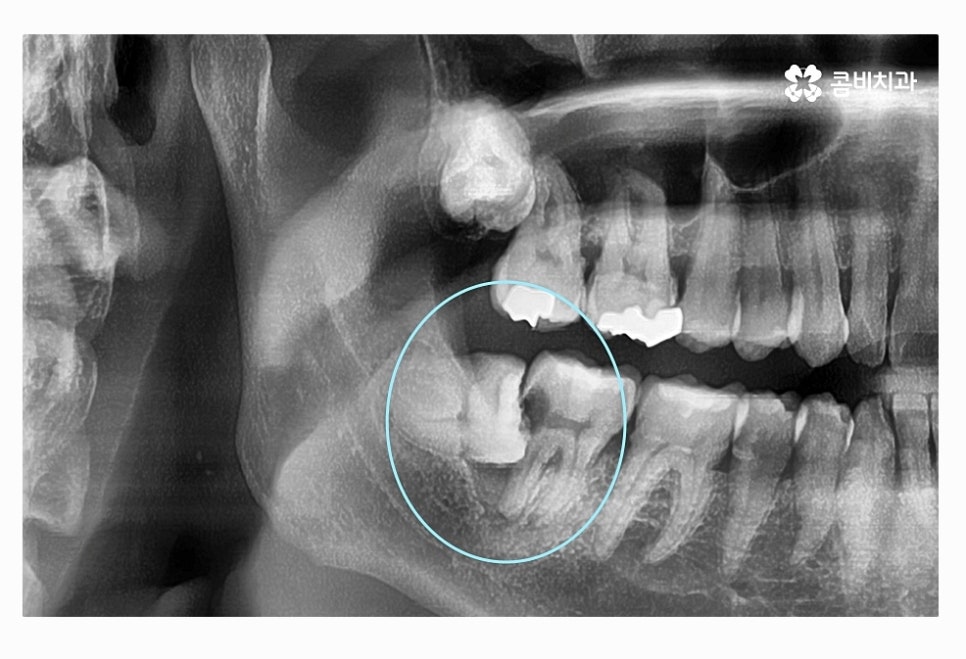

사랑니가 매복이 된 상태에서 위 사진처럼 부분적으로 돌출이 되어

사랑니 충치 심해지는 경우도 많고 주변 잇몸이 붓고

염증이 심해져서 잇몸에도 안 좋은 경우가 많이 있어요.

이처럼 사랑니 충치 심해지는 경우에 통증이나

입 냄새 등도 문제겠지만 멀쩡한 어금니 수명을 줄어들게

만들기도 하며 충치 전염, 치주질환 등으로

주변 치아에 안 좋은 영향을 주는 경우도 있는데요.